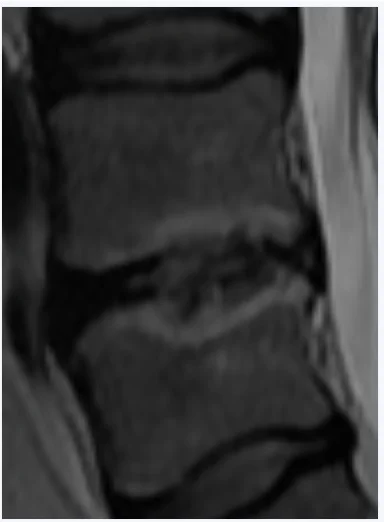

Mä pistän tohon pari croppausta noista magneettikuvista, jos ette oo nähny miltä "diskusdegeneraatio" näyttää. Ja vielä voimakasasteinen sellainen. Ei tarvi olla tosiaan radiologian erikoislääkäri nähdäkseen noista että vikaa on kun vertaa tota yhtä kohtaa muihin välilevyihin.

• MRIKoko.webp

MRIKoko.webp

10,7 KB · Katsottu: 828